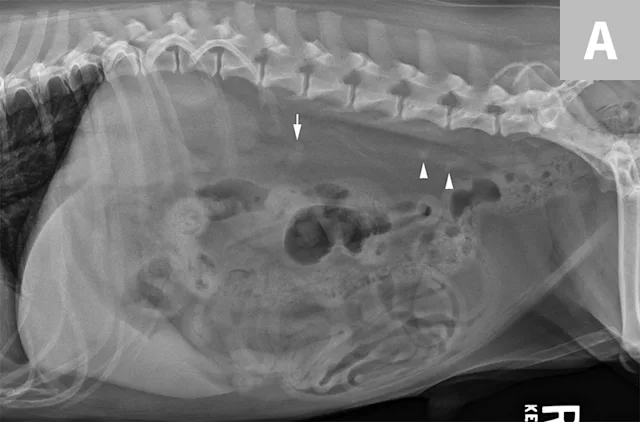

FIGURE 5A

Lateral abdominal radiograph of a dog with 2 well-defined, oval mineral opacities superimposed over the retroperitoneal space caudal and dorsal to the kidneys (arrows). Based on the ventrodorsal projection (not shown), these calculi were likely to be associated with the right ureter.

Ureteral calculi are a common cause of ureteral obstruction; localization of ureteral calculi is imperative prior to choosing appropriate management. While ureteral calculi have been reported as the most common cause of ureteral obstructions, other causes such as iatrogenic ligation, blood clots, tumor, strictures (congenital and acquired), solidified blood stones, and a circumcaval ureter have been reported.4-7

The obstruction can be located at any point of the ureter and can vary in severity. Normal ureters are typically not seen on ultrasonography due to their small size. The easiest way to locate a dilated ureter is to trace the ureter from the renal pelvis. In most cases, the ureter is dilated proximal to the site of an obstruction and tapers to a more normal appearance distal to the site of obstruction. Imaging can also reveal retroperitoneal effusion which can result from ureteritis and possible urine leakage.